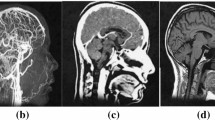

The original version of this article, published on 11 April 2019, unfortunately, contained a mistake. The following correction has therefore been made in the original: The image in Fig. 3c was wrong. The corrected figure is given below. The original article has been corrected.

The original version of this article was revised: The image in Figure 3c was wrong.